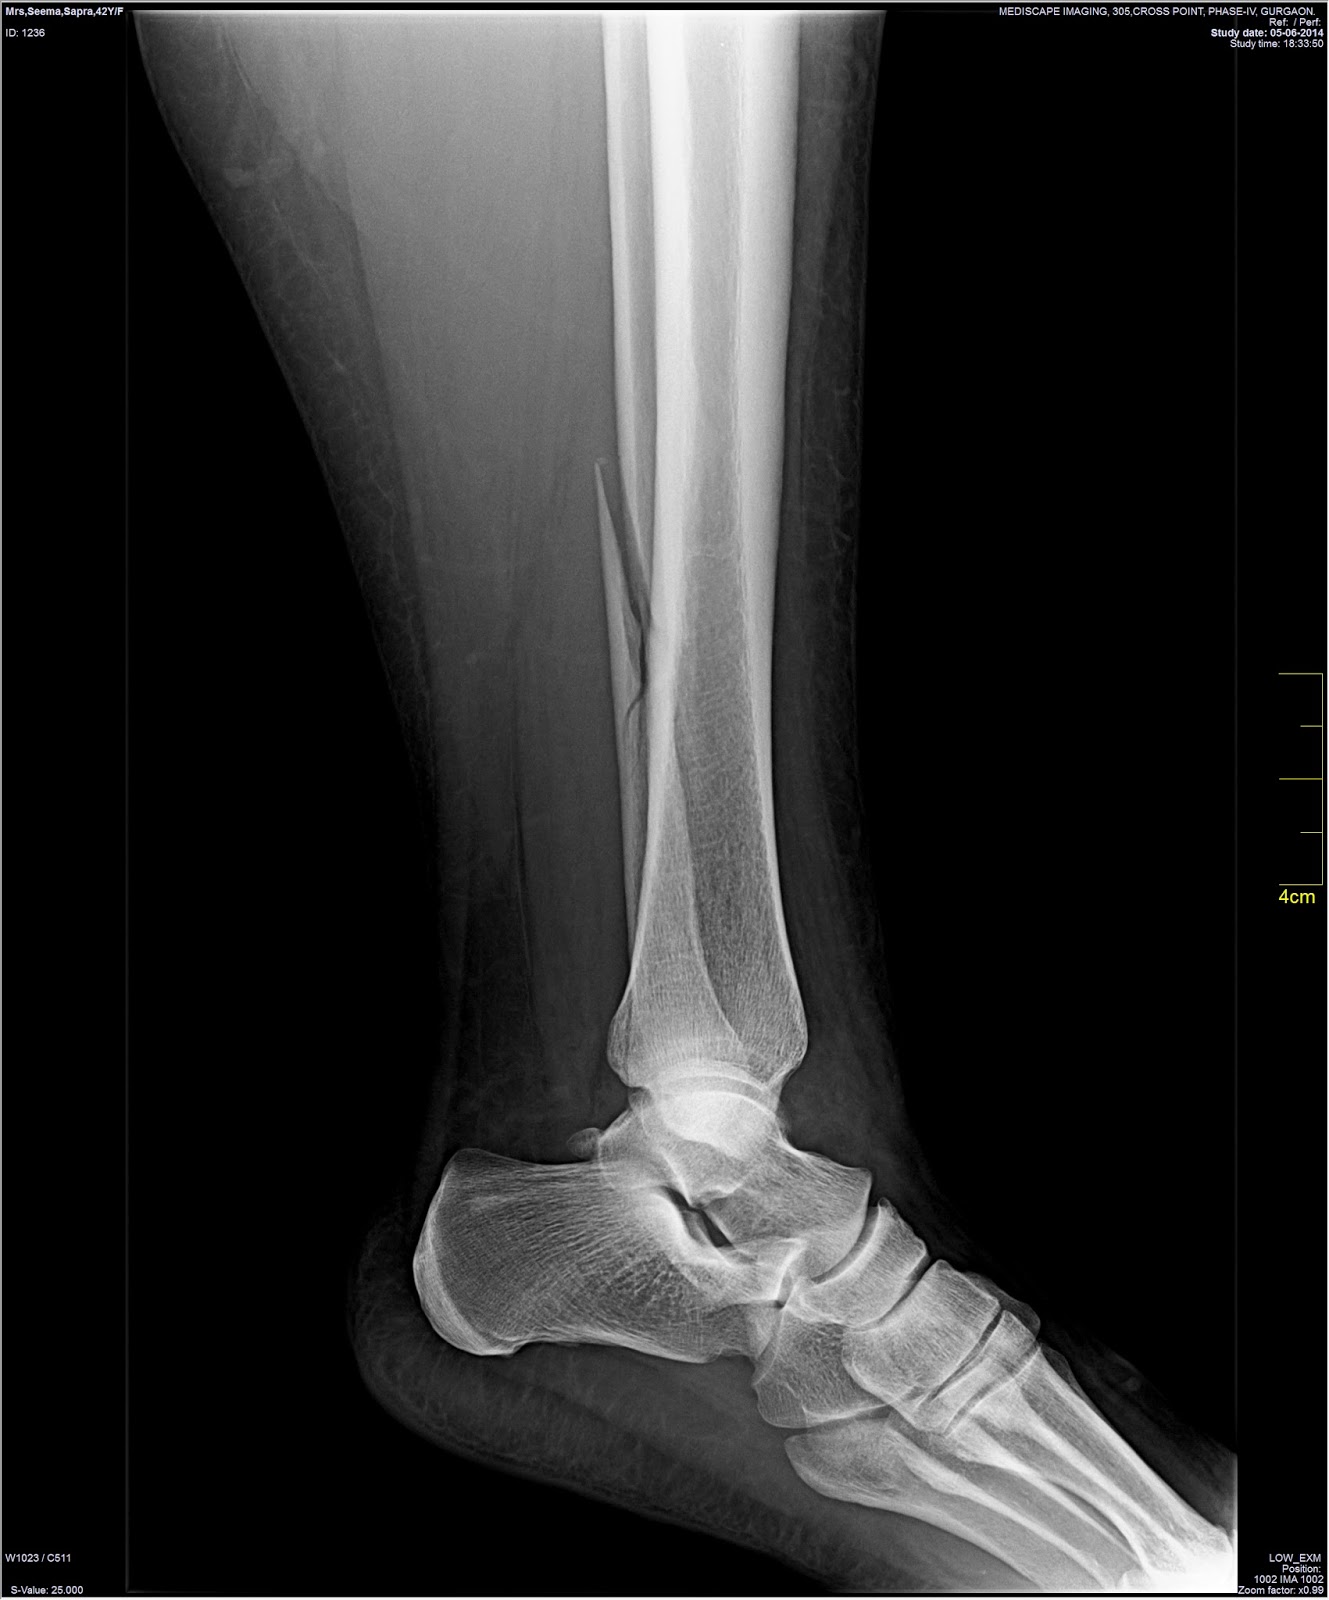

On 5 June 2014, Seema Sapra fractured her left fibula in a minor but awkward fall. She was taken to Artemis Hospital in Gurgaon and three doctors on that day confirmed only an un-displaced fibula fracture which did not require surgical intervention. Her left leg was placed in a cast. It was confirmed to Ms Sapra that there was no ankle injury.

Xrays dated 9 June 2014 taken after the ankle was twisted which show a dislocated ankle.

Xrays taken on 30 July 2014 from an external lab which were shown to Dr Anuj Malhotra at Fortis Hospital on 30 July 2014.